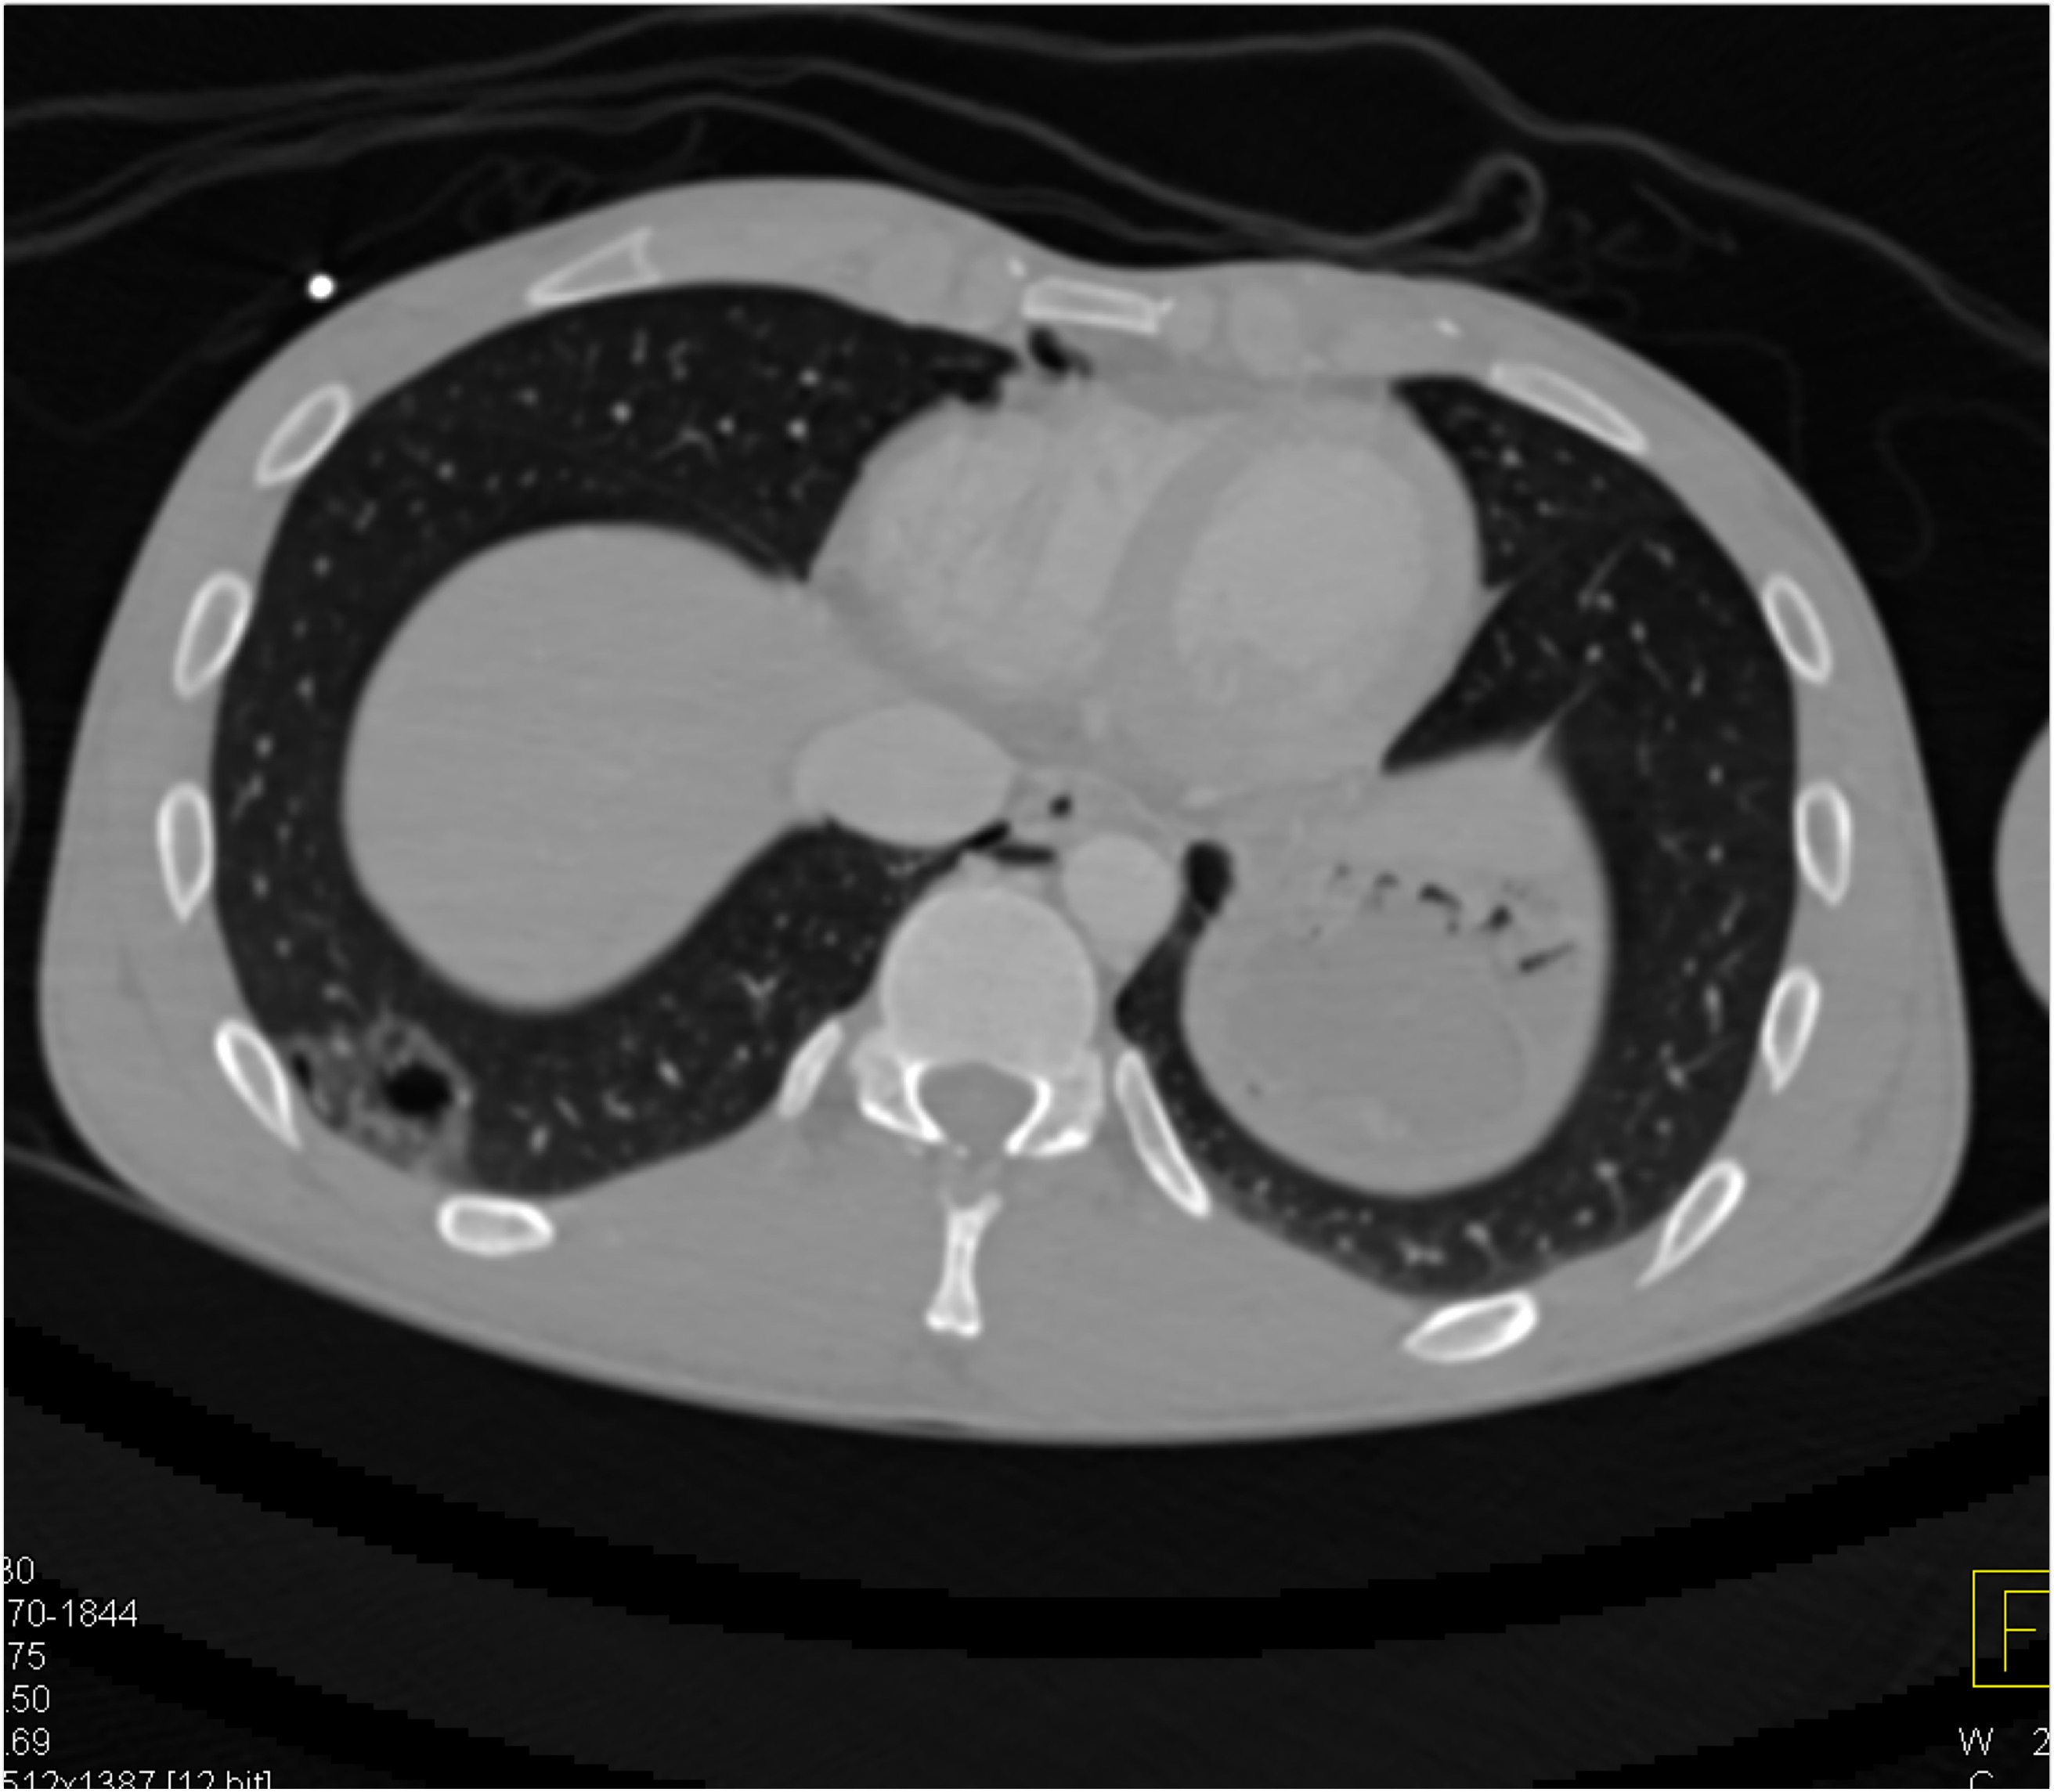

4) The mass in the right lower lung in this patient post trauma is

pulmonary contusion

lung infarct

adenocarcinoma

pulmonary laceration